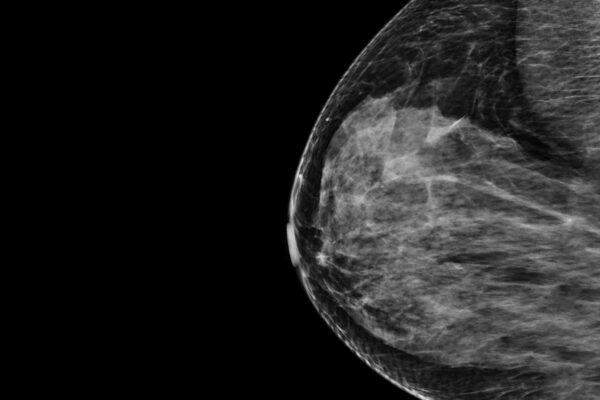

The system analyzes mammograms to produce a risk score estimating the likelihood that a woman will develop breast cancer over the next five years. The technology is compatible with both types of mammogram imaging available: the four 2D views of the breast produced by full-field digital mammography and the synthetic 3D view of the breast produced by digital breast tomosynthesis. Importantly, the system produces an absolute five-year risk that makes it possible to compare a woman’s risk to an average risk based on national breast cancer incidence rates. This provides a meaningful estimate that is aligned with the U.S. national risk reduction guidelines, so that clinicians will know what steps to take next if a woman’s risk is elevated.

The software is a pre-trained machine learning system that analyzes mammogram images and provides an estimate of how likely a patient is to develop breast cancer over the next five years, based solely on images and a woman’s age. According to the developers, Prognosia Breast estimates a person’s five-year risk of developing breast cancer 2.2 times more accurately than the standard method, which is based on questionnaires that consider factors such as age, race and family history. The system was trained on past mammograms from tens of thousands of individuals who underwent breast cancer screening through Siteman Cancer Center. Some of them went on to develop cancer, teaching the system what to look for in the earliest stages of tumor development. Such early signs of disease can’t be perceived even by a well-trained human eye.

The device produces a five-year risk score that is intended to complement, not replace, the analysis provided by radiologists, who will continue to review the mammograms following standard protocols. According to the American Society of Clinical Oncology and the U.S. Preventive Services Task Force, a five-year risk score of 3% or higher is considered elevated. According to guidelines from these organizations, women with elevated scores should be referred to specialists who can further advise them on their options for additional screening and prevention strategies.